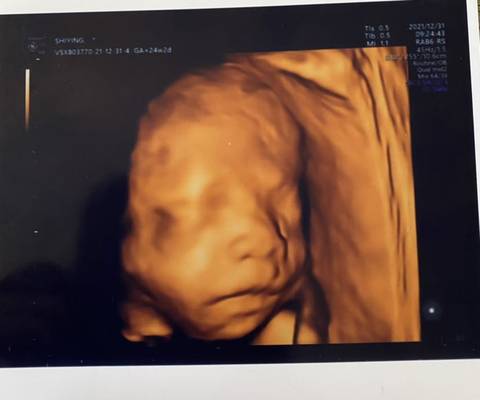

有会看????????的吗?纯属好奇????

男孩,看样子就是了

看不出来,这个单上的数据是很难直接判断男孩还是女孩的哦,其实只要孩子健健康康就好,生下来才最准

你好。我们是判断不了男宝宝跟女宝宝的,孕期定期检查,我觉得宝宝健康就好的。祝心想事成 。

你好,对于宝宝是男孩女孩虽然很好奇,但是怀孕的单子、数据、表现是判断不出来的,在这也愿你心想事成。